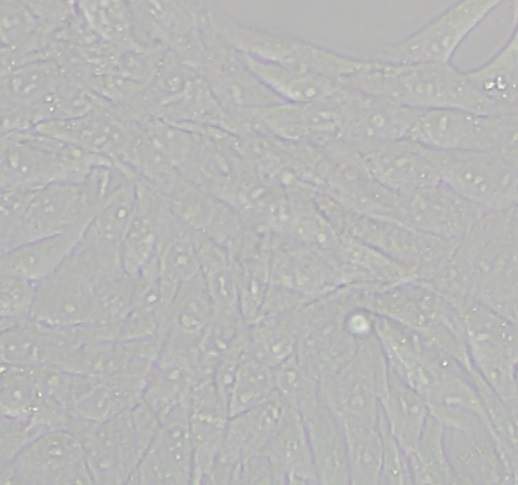

LX-2细胞活化问题 已有1人参与